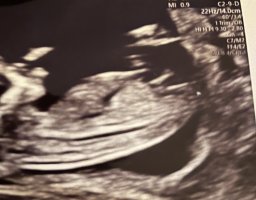

Du er fortsatt 12+1.. Du vet jo fra innsett. Men at fosteret vokser i rykk å napp er ikke uvanlig.. blitt målt lengre alle gangene.Regnet ut i fra IVF egginnsett 12+1, men jordmor mente 12+4 etter å ha målt fosteret da disse bildene ble tatt

Regnet ut i fra IVF egginnsett 12+1, men jordmor mente 12+4 etter å ha målt fosteret da disse bildene ble tatt

Jeg syntes det var litt rart at hun mente det var noen dager eldre når det er snakk om innsett, syntes også det var rart at hun fikk samme termindato når hun mente at jeg er 3 dager lengre på veiDu er fortsatt 12+1.. Du vet jo fra innsett. Men at fosteret vokser i rykk å napp er ikke uvanlig.. blitt målt lengre alle gangene.![]()

Det er ikke så rart, da de måler alderen utfra størrelse.. de vokser i rykk og napp så derfor har det ikke så mye å si for oss IVF gravide. Du får ikke ny termindato uansett fordi du er gravid ved IVF. Det er 100% sikkert hvor langt du er på vei så din termindato skal bli stående uansettJeg syntes det var litt rart at hun mente det var noen dager eldre når det er snakk om innsett, syntes også det var rart at hun fikk samme termindato når hun mente at jeg er 3 dager lengre på vei

Det er veldig tidlig for å se kjønn, men det ser ut som en jente nå, men det kan endre seg. Det er veldig små marginer for å måle mer eller mindre så du er nok 12+1, noen vokser litt mer og andre vokser litt mindre også, ofte er gutter litt større enn jenter også. Jeg tror kanskje nuben vil reise seg litt på denne og at det er en gutt, men enn så lenge ser det ut som jenteNoen som kan se noe kjønn på disse bildene?